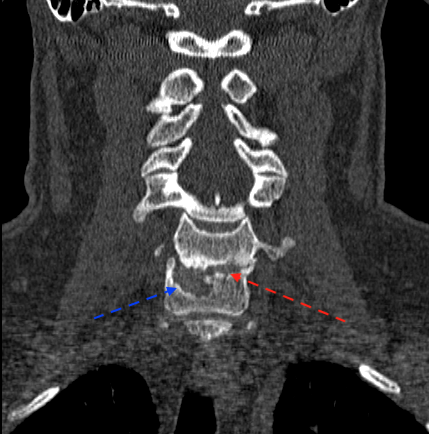

La flecha azul indica el hundimiento/resorción del platillo C7 en lado derecho, (la prótesis se ubicó muy lateral); el lado izquierdo (flecha roja) parece íntegro.

En TC sagital se aprecia ausencia de fusión y ubicación de la caja en mitad anterior (incluso con extensión parcial)